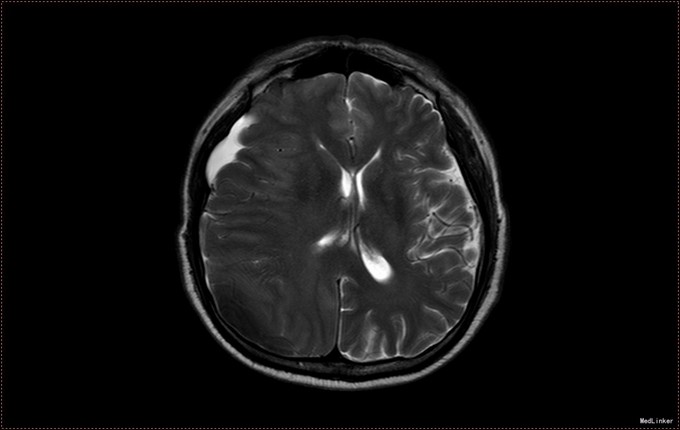

患者,男,53岁。以“左侧肢体疼痛伴无力1周”为主诉入院。患者1周前无明显诱因出现左侧肢体无力,伴酸痛,头部闷胀感,症状持续不缓解,于我院就诊,行头部CT及MR提示右侧顶枕叶硬膜下血肿。右侧额颞叶蛛网膜囊肿。患者为求进一步治疗,急诊以“硬膜下血肿”为诊断,收入病房。患者病来精神状态差,饮食睡眠可,二便可,体重无明显变化。否认近期头部外伤史。

入院查体:T:36.5℃ ,P:68次/分 ,BP:130/80mmHg , R:16次/分。步入病房,自主体位。神清语明,问答准确,查体合作,精神状态良好,定向力完整。粗测视野正常,双侧瞳孔等大正圆,D≈3.0mm,双侧眼球活动自如,对光反射灵敏。四肢活动自如,左侧肢体肌力V-级,右侧肢体肌力Ⅴ级,肌张力正常。深浅感觉检查未见异常。头CT及MR提示右侧颞极蛛网膜囊肿,右侧亚急性硬膜下血肿

患者诊断明确,完善术前检查行局麻右侧钻孔冲洗引流术,予常规治疗。术后3天拔管,复查头CT硬膜下血肿消失,但脑组织膨胀不良。患者左侧肢体肌力恢复正常,无头晕头沉症状,顺利出院。